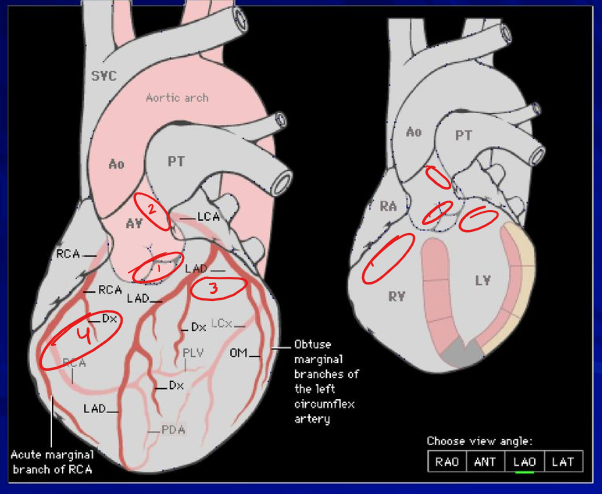

What is the correctorder of a quad bypass as they would appear on the Aorta

SVG

OM

RCA

LAD

DIAG

What vessel can be viewed on the anterior side of the heart